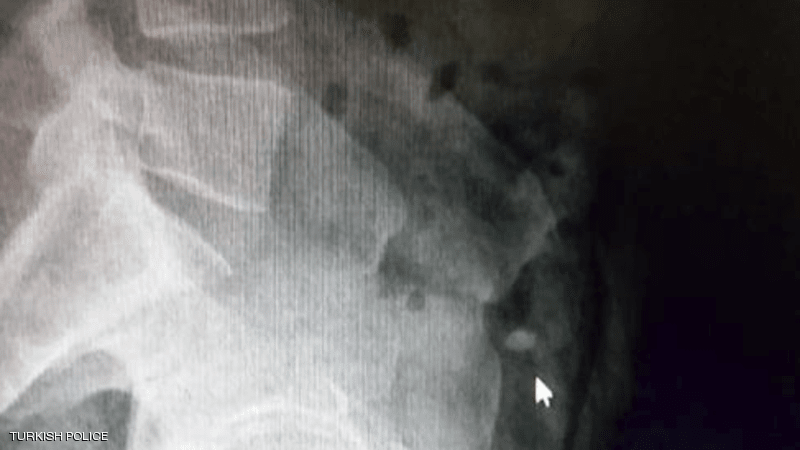

وأمرت الشرطة بنقل السارق إلى المستشفى، من أجل إجراء عملية جراحية للعثور على الخاتم، ما لم يعد الأيرلندي الخاتم بـ”الطريقة الطبيعية”.

وقد قفز مرارا في المستشفى لتحريك الخاتم في أحشائه لمدة 36 ساعة، لكن جهوده كانت بلا جدوى، وبعد ذلك لجأت السلطات إلى استخراج الألماس عبر عملية جراحية.